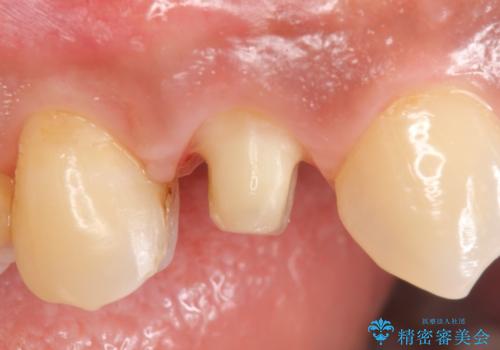

- 右上の歯茎の腫れが引かないので診て欲しいといらっしゃった方の症例です。

検査の結果、右上4番目の歯は神経が死んでおり、そのせいで歯茎に膿の出口が出来ていることがわかりました。

右上4は根管治療を行い、オールセラミッククラウンによる補綴を行いました。